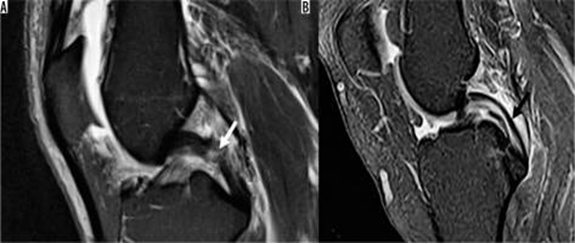

Hình 3. Hình ảnh cộng hưởng từ có trọng số mật độ proton sagital có sụn chêm bên dạng đĩa với tín hiệu tăng trong sụn.

Hình 4. Rách sụn chêm, nang sụn chêm. Hình ảnh coronal xóa mỡ có u nang nhỏ (mũi tên đen) tiếp giáp với thân của sụn chêm bên có vết rách liên quan đến sụn chêm (mũi tên trắng)

Hình 5. Vết rách ngang sụn với mảnh di lệch. Hình ảnh pd xóa mỡ với vết rách sụn chêm giữa và mảnh di lệch (mũi tên) nằm giữa dây chằng chéo giữa và mâm chày giữa.